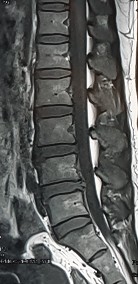

1. Hình ảnh khảo sát dẫn truyền thần kinh, điện cơ đồ và MRI (thực hiện trên mẫu nghiên cứu: bệnh nhân Nguyễn Văn H., mã số bệnh nhân 731711).

Bệnh nhân H., khi khám lâm sàng có biểu hiện tổn thương rễ thần kinh L3, L4, L5. Kết quả xét nghiệm điện cơ thấy: dẫn truyền thần kinh bình thường, nhưng kết quả khi điện cơ kim có biểu hiện tổn thương rễ thần kinh L4 . Kết quả chụp cộng hưởng từ là tổn thương thoát vị L4 – L5 . Như vậy, trên bệnh nhân này vị trí tổn thương thực tế khi kết hợp phối hợp giữa khám lâm sàng, chẩn đoán hình ảnh và chẩn đoán chức năng là vị trí rễ thần kinh L4.

Hình ảnh thoát vị đĩa đệm trên phim chụp MRI.